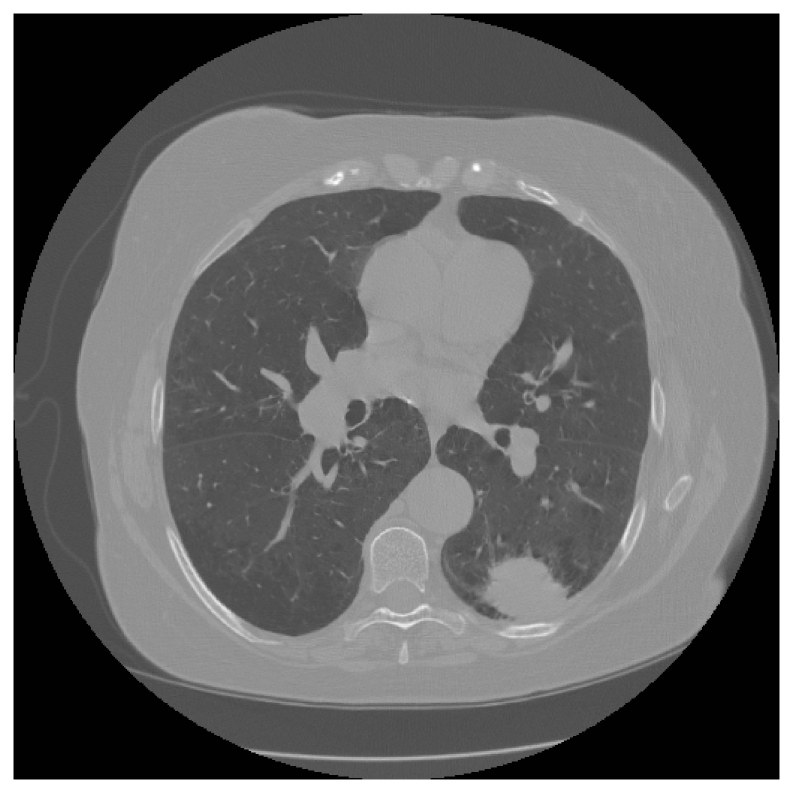

4.2.1 Sparse-view CT

We first evaluate the performance of SkEI using a single sample from the resized sparse-view CT 100 dataset and then further compare this method with DIP and EI. For the vanilla EI method, we use the architecture suggested in chen2021equivariant to achieve the best performance and build the DIP using the same residual U-Net used in EI. For the sketched EI, we choose the subsampling sketch as our SS, which splits the measurement operator into NN minibatches, AS1,AS2ASNA_{S_{1}},A_{S_{2}}...A_{S_{N}} from interleaved angles. In each iteration, we randomly select one of the minibatch and perform the update. We test on the choices N=2,5,10,20N=2,5,10,20 respectively here. As shown in Figure 2, the baseline DIP frameworks deliver only modest reconstruction fidelity in our study, while the incorporation of the EI regularizer improves reconstruction precision. In particular, the sketch-guided EI model with N=10N=10 achieves the highest reconstruction quality of all the evaluated methods. To further study the impacts of the sketching operation, we performed ablation experiments with four different sketch sizes as reported in Figure 3 and Figure 4(a). We can observe that the results for Sketched EI are slightly better than full EI (vanilla EI), for the number of minibatch splits chosen to be 2, 5, 10, or 20 (corresponds to 50%, 20%, 10% and 5% of origin, respectively), and reach the best at splits 10. The result would deteriorate if we choose to sketch over aggressively (20 splits in this setting), indicating a phase transition.

Figure 2: CT Images (with corresponding PSNR) reconstructed by DIP, EI and our Sketched EI. DIP-full and EI-full use 100 CT scans, while EI-Sketch-10% means only 10% of 100 CT scans used per iteration. (*) denotes the baseline.